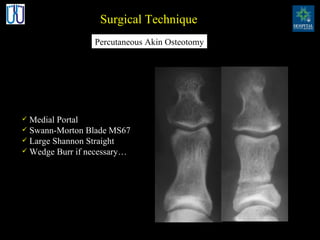

Surgical Technique Medial Portal Swann-Morton Blade MS67 Large Shannon Straight Wedge Burr if necessary… Percutaneous Akin Osteotomy

Surgical Technique MedialPortal Swann-Morton Blade MS67 Large Shannon Straight Wedge Burr if necessary… Percutaneous Akin Osteotomy